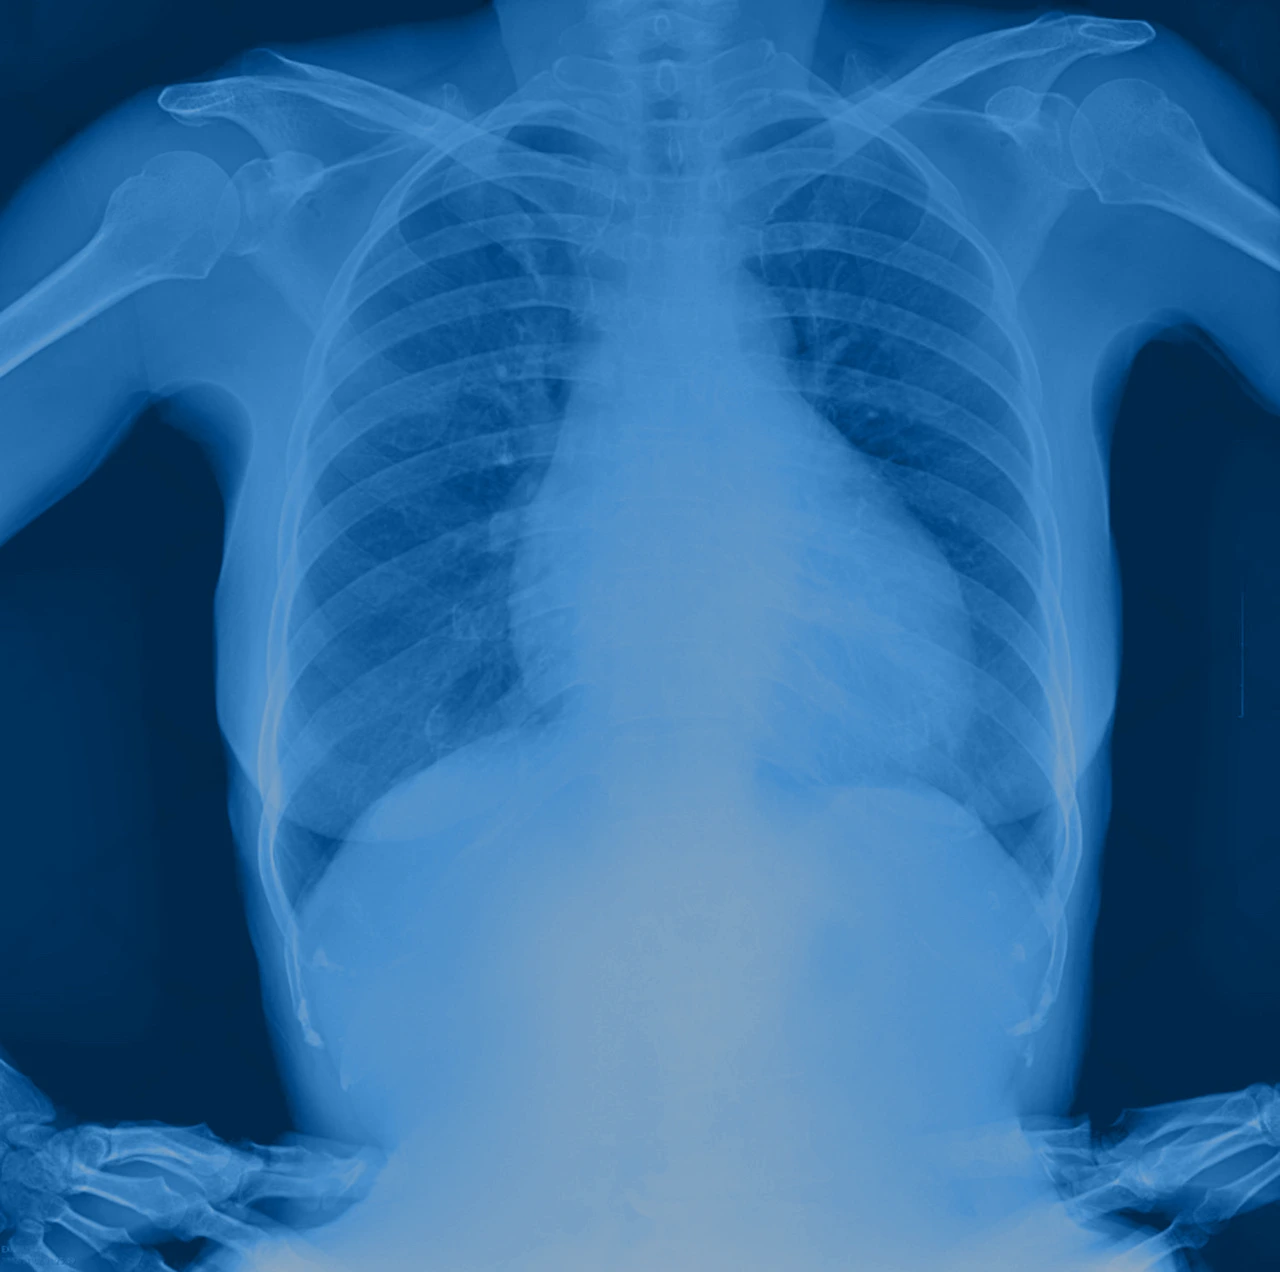

• Radiografía de tórax: sirve para observar el tamaño del corazón y signos de congestión pulmonar.

Radiografía de tórax en un bebé como estudio para identificar la presencia o ausencia de retorno venoso pulmonar.